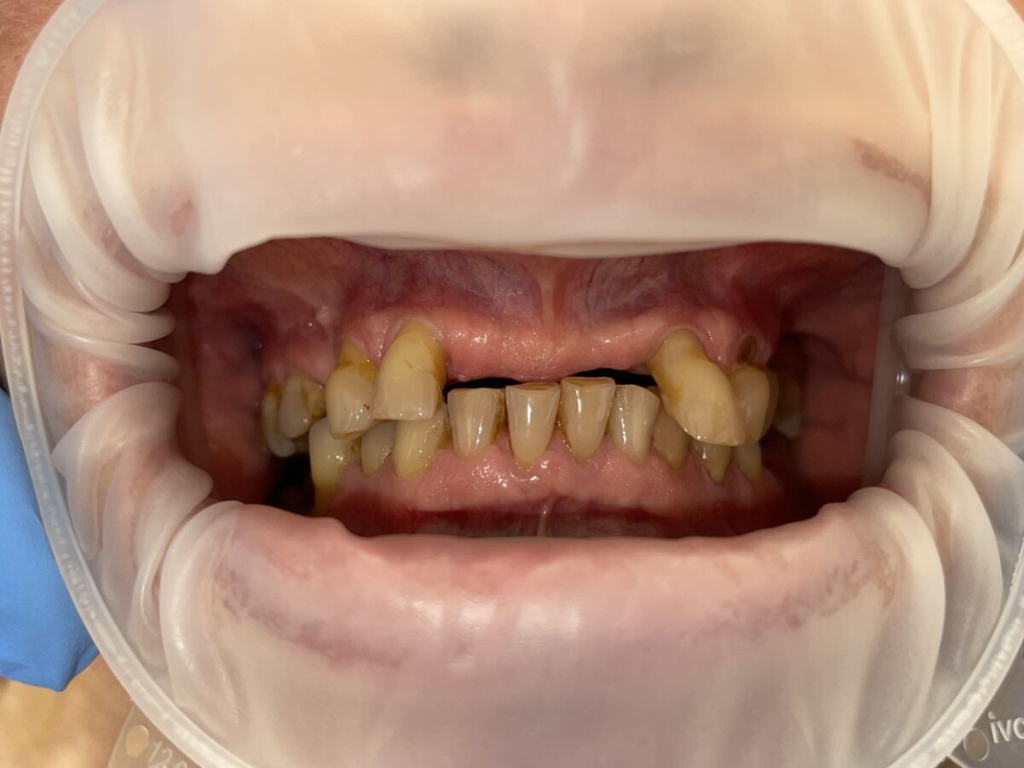

Výsledky, které mluví za vše

- fotografie před/po

Technika All-on-X — I. fáze

Ukázky práce před a po

ДоПосле